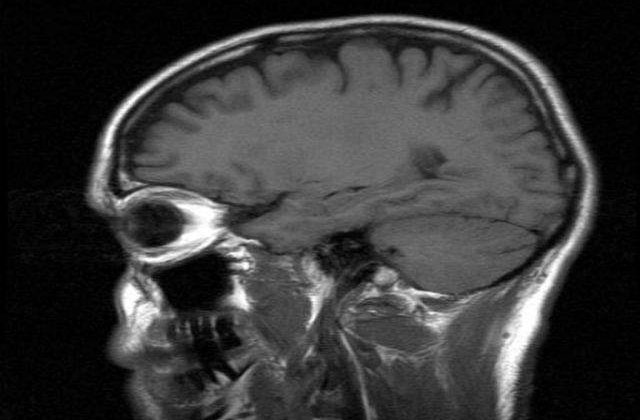

In acest studiu, coordonat de medicul Eric Kandel, laureat al premiului Nobel pentru medicina pe anul 2000, cercetatorii de la Universitatea New York au analizat mai intai, post-mortem, creierele a opt persoane decedate intre varstele de 33 si 88 ani. Analizele efectuate pe tesuturi cerebrale au permis izolarea unei proteine a carei sinteza scade considerabil odata cu inaintarea in varsta, scrie mediafax.